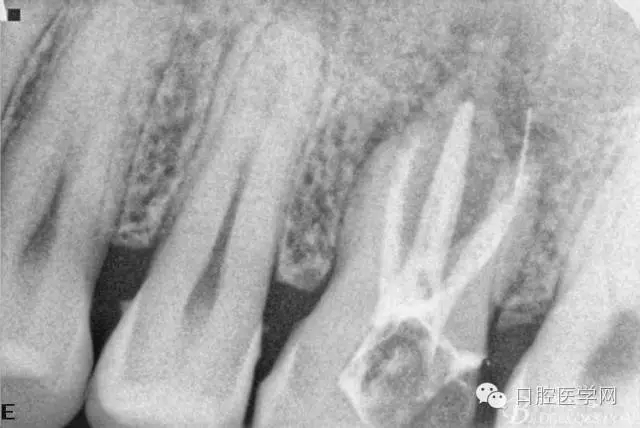

檢查26Ⅲ°松動(頰舌向、近遠中向、頜齦向)。X線片顯示根尖周彌漫性炎性陰影。

初診X線片